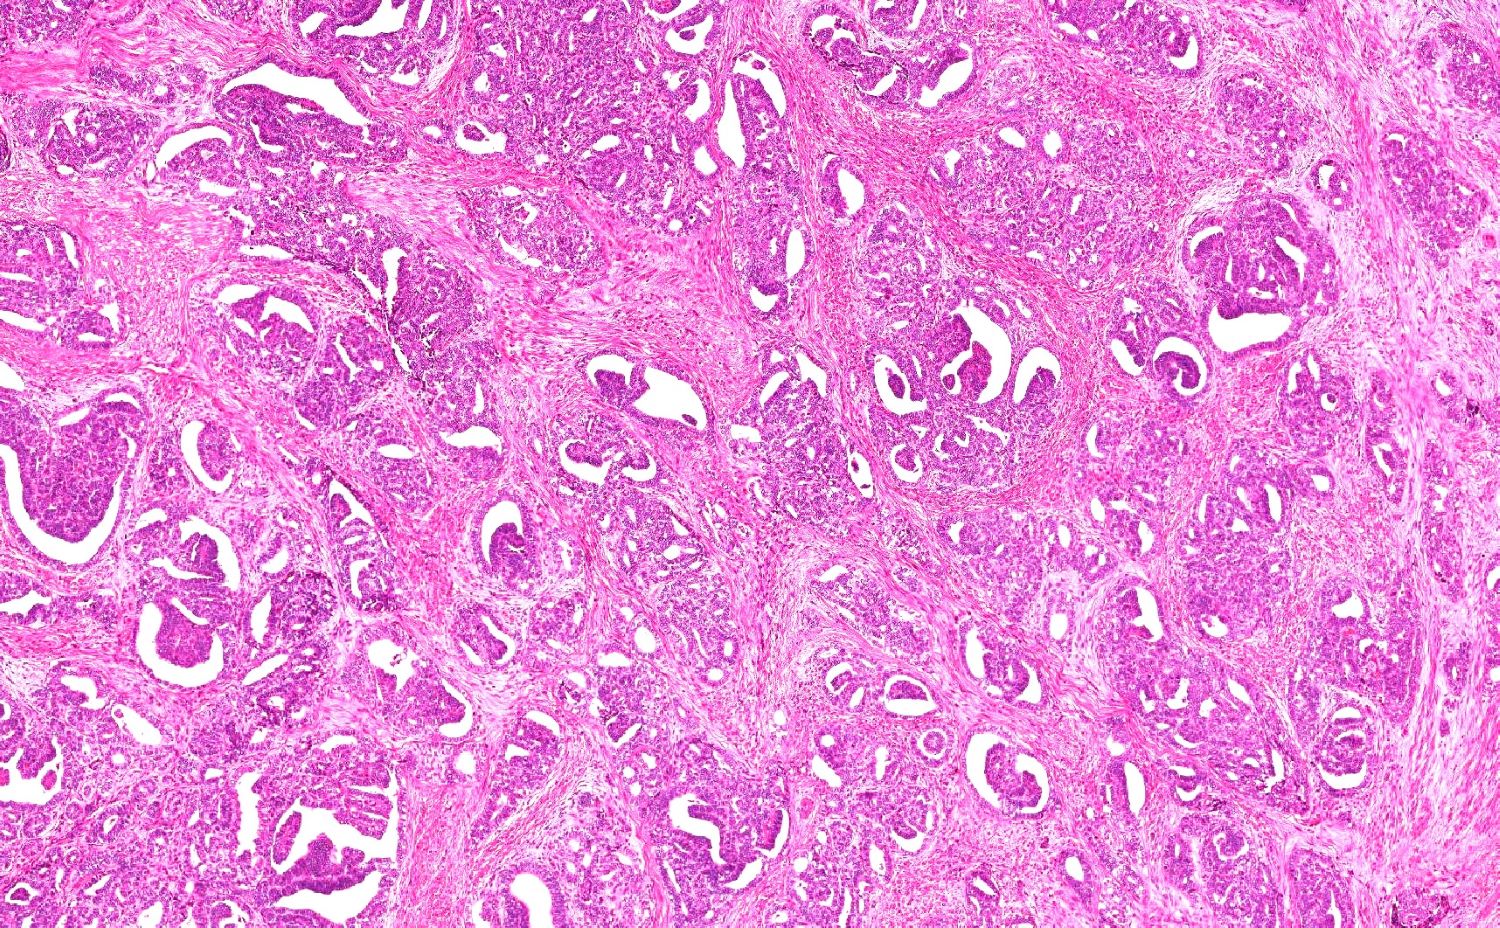

- Variety of histologic patterns that may be present within the same tumor

- Most frequently small tubules with ductal / glandular growth

- Papillary, solid growth, trabecular, retiform, sex cord-like, sieve-like, glomeruloid and spindle cell areas have all been described

- Luminal eosinophilic secretions are characteristic but not always identified

- Tumor cells can be flattened, cuboidal or columnar with mild to moderate cytological atypia

- Clear cell features can be seen but are less common

- High grade cytological atypia is usually not a predominant feature

- Nuclei show vesicular chromatin and nuclear grooves

- Sarcomatoid transformation has been seen in rare instances

- Squamous, ciliated or mucinous differentiation (metaplasia) are not present and there are no associated mesonephric remnants (J Clin Med 2021;10:698)

Microscopic (histologic) images

Contributed by Daniel Graham, M.D., Adele Wong, M.B., B.Ch., B.A.O. and Lucy Ma, M.D.